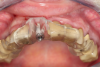

Fig 36. Anterior central view.

Figure 36

Fig 42. Occlusal view of prepared implants.

Figure 42